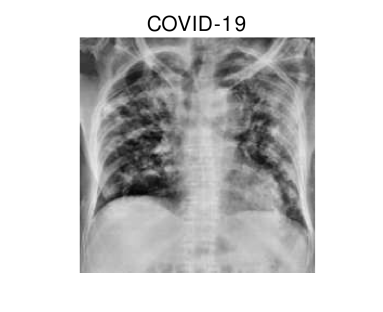

In hospitals, chest X-rays can mitigate these drawbacks by enabling a fast and reliable diagnosis. Figure 1 shows chest X-ray scans of healthy (top) and COVID-19 (bottom) patients in direct comparison. Even though patchy consolidations are recognizable in the COVID-19 scans, such X-rays remain challenging to interpret. Specialists, however, are able to identify the severity of a case early on and can take measures without waiting for lab results.